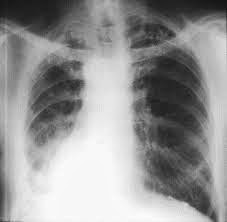

Before and After Asbestos Lungs

Lung Cancer

Mesothelioma

Asbestosis